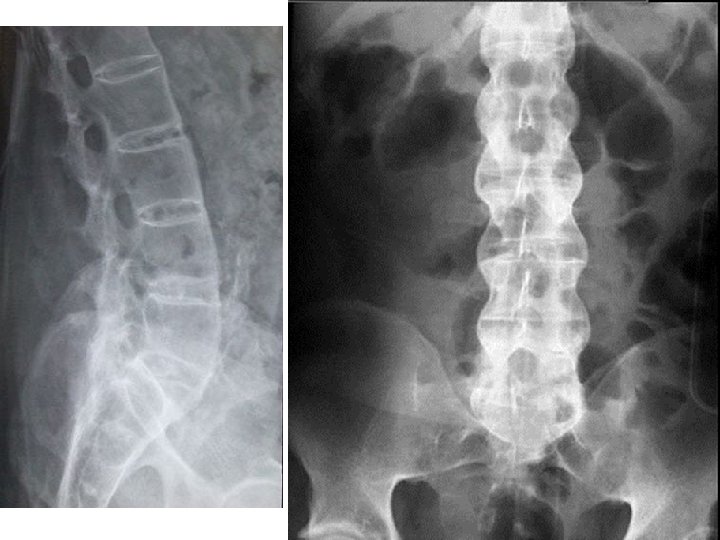

Остеохондроз позвоночника l l Дегенеративное поражение хряща межпозвонкового диска с реактивными изменениями со стороны тел позвонков. Первично здесь повреждение студенистого (пульпозного) ядра с последующей дегенерацией фиброзного кольца, образованием в нем трещин и пролабированием фрагментов студенистого ядра. В условиях измененной подвижности позвоночного сегмента наступают изменения в межпозвонковых суставах, развивается спондилоартроз. Спондилез - анкилоз позвонков - это общий неспецифический термин, часто употребляемый по отношению к различным поражениям позвоночника дегенеративной природы.

Методы исследования l l l Рентгенография. Компьютерная томография - диагностика поражений костных структур позвоночника и позвоночного стеноза, степень визуализации грыж дисков незначительна и уступает магнитно-резонансной томографии. Информативность метода снижается также тем, что производятся только поперечные срезы, поэтому необходимо знать уровень поражения для уменьшения лучевой нагрузки на пациента. Магнитно-резонансная томография - метод выбора для выявления грыж межпозвонкового диска и протрузии диска и в отличие от КТ не связана с лучевой нагрузкой. МРТ дает возможность проведения как поперечных, так и продольных срезов, что увеличивает информативность. МРТ визуализирует компрессию корешков и степень дегенерации самого диска (протрузию, пролапс и секвестрацию). При МРТ четко разграничиваются экстра- и интрадуральные структуры и хорошо выявляются латеральные грыжи диска.

Рентгенологические критерии